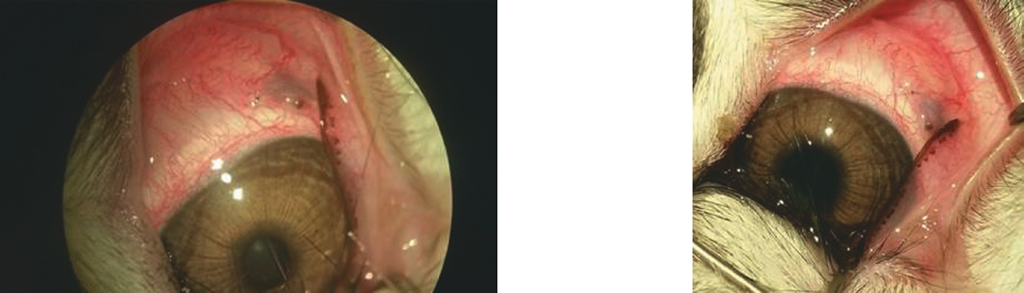

При оценке макроскопических препаратов в первой контрольной точке исследования (30 суток после оперативного вмешательства) во всех случаях полиуретановая трубка была имплантирована в СХП через разрез склеры и проходила под склерой на расстоянии 6–7 мм от лимба, дистальный конец трубки располагался в зоне экватора на уровне сосудистой оболочки глаза. Проксимальный конец трубки был фиксирован узловым швом к склере, воспалительные явления со стороны конъюнктивы и склеры в месте выхода полиуретановой трубки отсутствовали (рис. 9).

Рис. 9. Макропрепарат глаза экспериментального животного (стрелкой указано место выхода дренажной полиуретановой трубки через склеростому)

Fig. 9. Gross specimen of the experimental animal’s eye (the arrow shows the site of polyurethane drainage tube exit through a sclerostomy)

При оценке макроскопических препаратов через 90 суток после оперативного вмешательства (вторая контрольная точка исследования) во всех случаях полиуретановая трубка была имплантирована в СХП через разрез склеры на расстоянии 6–7 мм от лимба и располагалась в зоне экватора на уровне сосудистой оболочки глаза. Наружный конец трубки фиксирован узловым швом к склере, воспалительные явления со стороны конъюнктивы и склеры в месте выхода имплантата не определялись.

На глазном дне визуализировалось место залегания имплантата с точкой введения в 5–6 мм от лимба, проходящего в сторону заднего полюса глаза к диску зрительного нерва. В проекции имплантата определялась неравномерная пигментация, менее интенсивная по отношению к окружающим отделам сетчатки (рис. 12).

Рис. 12. Макропрепарат глазного дна экспериментальных животных в проекции залегания дренажной полиуретановой трубки (вторая контрольная точка исследования)

Fig. 12. Gross specimen of the eye fundus of experimental animals in the projection of a polyurethane drainage tube position (second control point of the study)